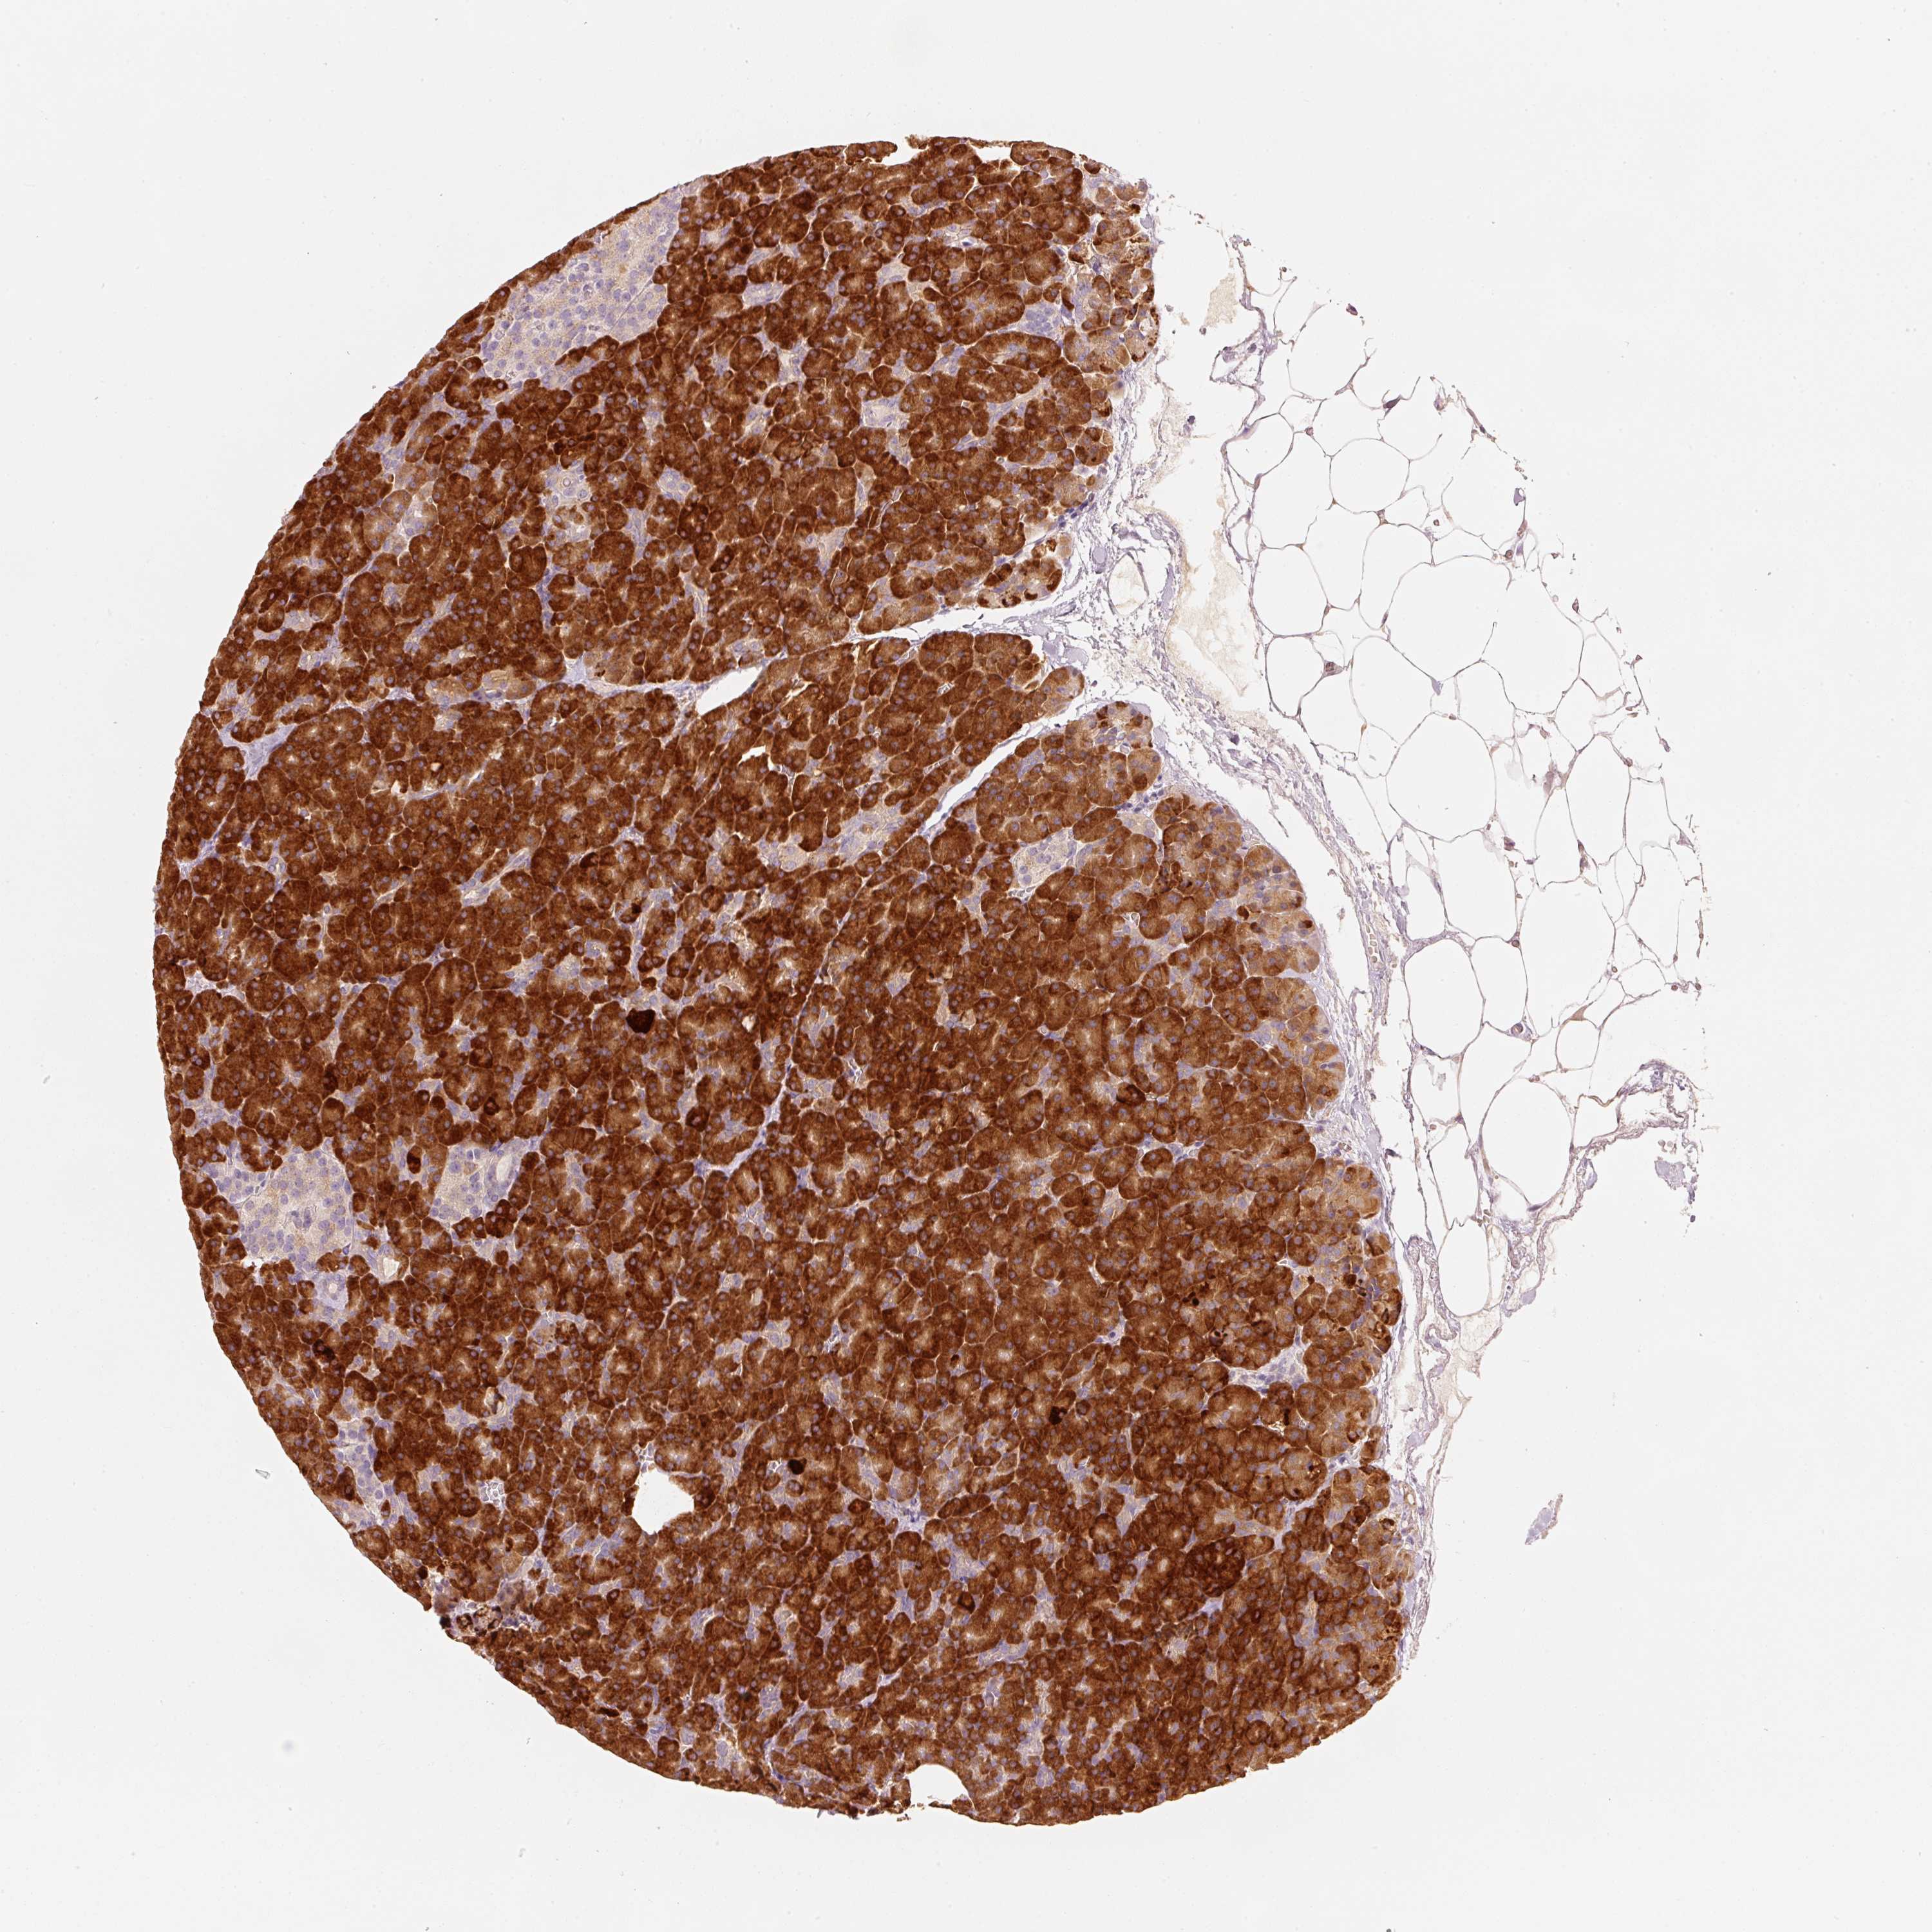

OR13C3